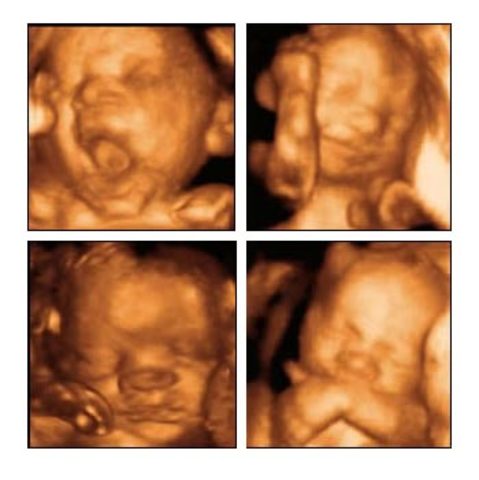

• Ecografias en 3D

Ecografias en 3D

El creador fue Doctor Samanch.

Las eco grafías en 3d nos ha sirvido para observar la morfología uterina, ademas de permitirnos tener un control del desarrollo del feto en tiempo real, permitiendo también diagnosticar posibles falencias que este presentando durante la gestacion. <ahref='http://www.ecografias3d.com/index.php?option=com_content&view=article&id=2&Itemid=2&lang=es' >Ecografias.</a>